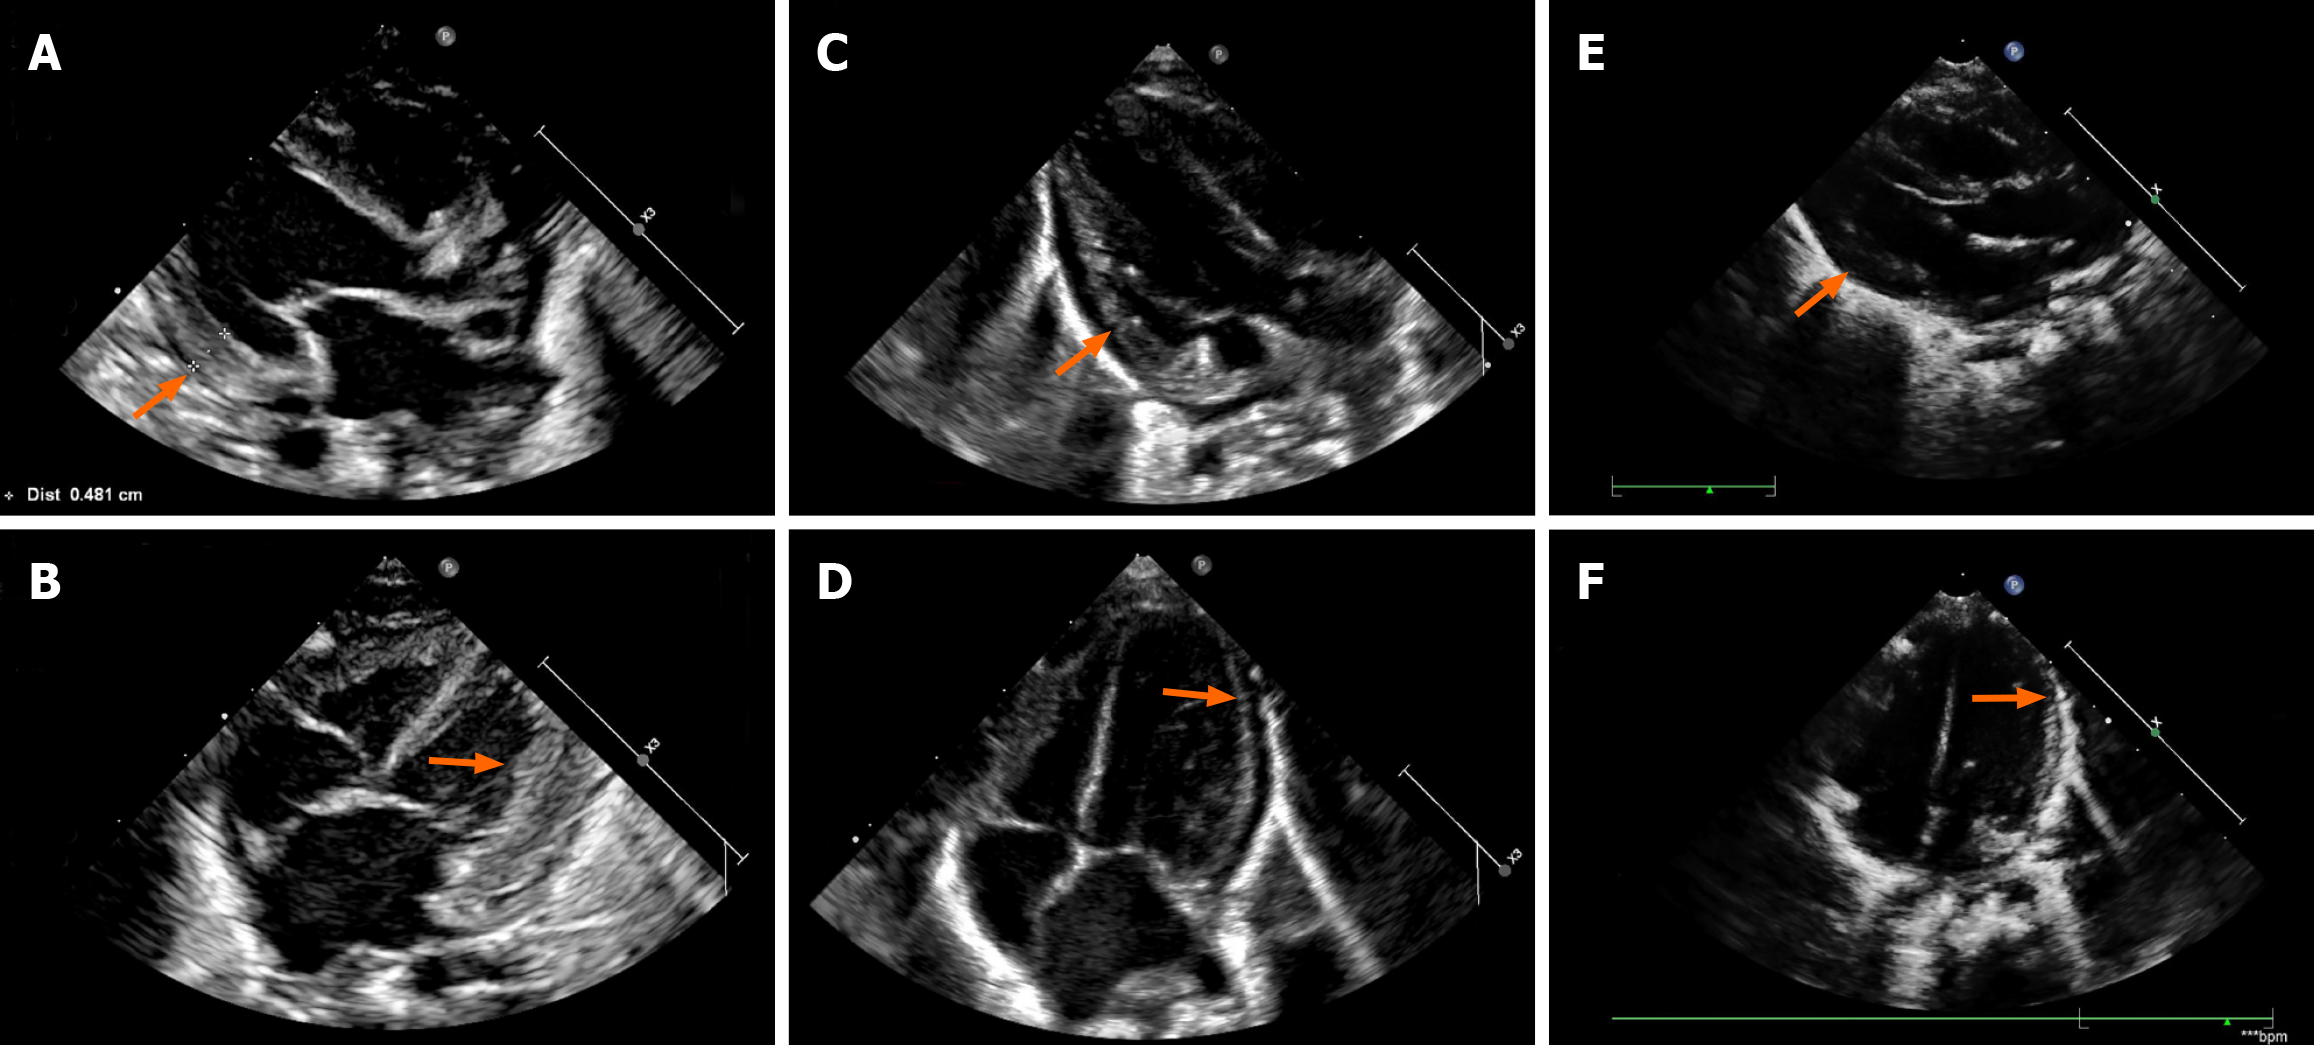

Figure 2 Cardiac color doppler ultrasound changes during levothyroxine treatment.

A and B: Cardiac ultrasound (pre-levothyroxine and 2 days post-levothyroxine) revealed left ventricular hypertrophy and left heart enlargement (orange arrows); C and D: Ultrasound (29 days post-levothyroxine) showed improvement in left heart size and left ventricular hypertrophy (orange arrows); E and F: Ultrasound (92 days post-levothyroxine) showed normalized cardiac structure (orange arrows).